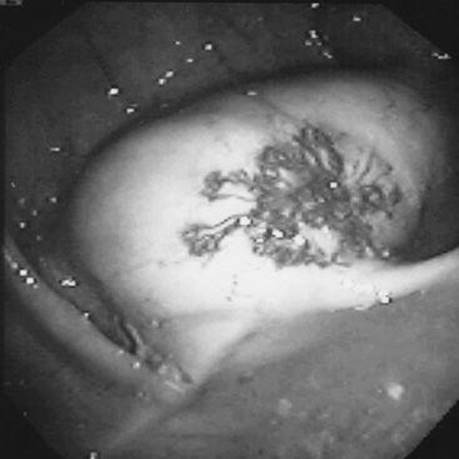

A 35-year-old man presents with massive hematemesis and anemia following an episode of protracted retching. What does the figure show?

Figure 1-2 See also color plate.

Mallory–Weiss tear.